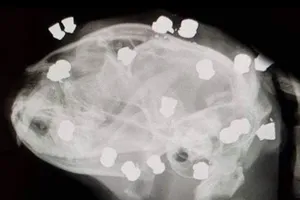

Chú mèo sống sót kỳ diệu dù bị bắn trúng 18 viên đạn